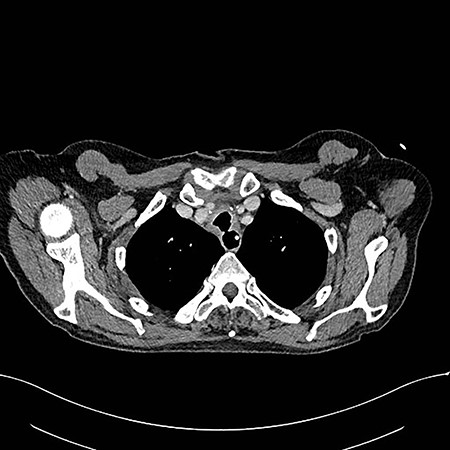

On examination, the patient had no obvious abnormality in the valve puncture. The stoma site was normal except for some crusting around the edges. A marked abnormality on the tracheal wall ~6 cm inferior to the stoma site was revealed, through a flexible nasal endoscopic examination. The abnormality was later confirmed to be a TOF. The patient underwent a computed tomography (CT) scan to delineate the surrounding anatomy as to facilitate the planning of the surgery (Figs 2–4).

Axial reconstruction post contrast CT neck and thorax images with 4 mm defect/tracheoesophageal fistula located 8–9 cm from tracheostomy level and 12 cm proximal to the carina.